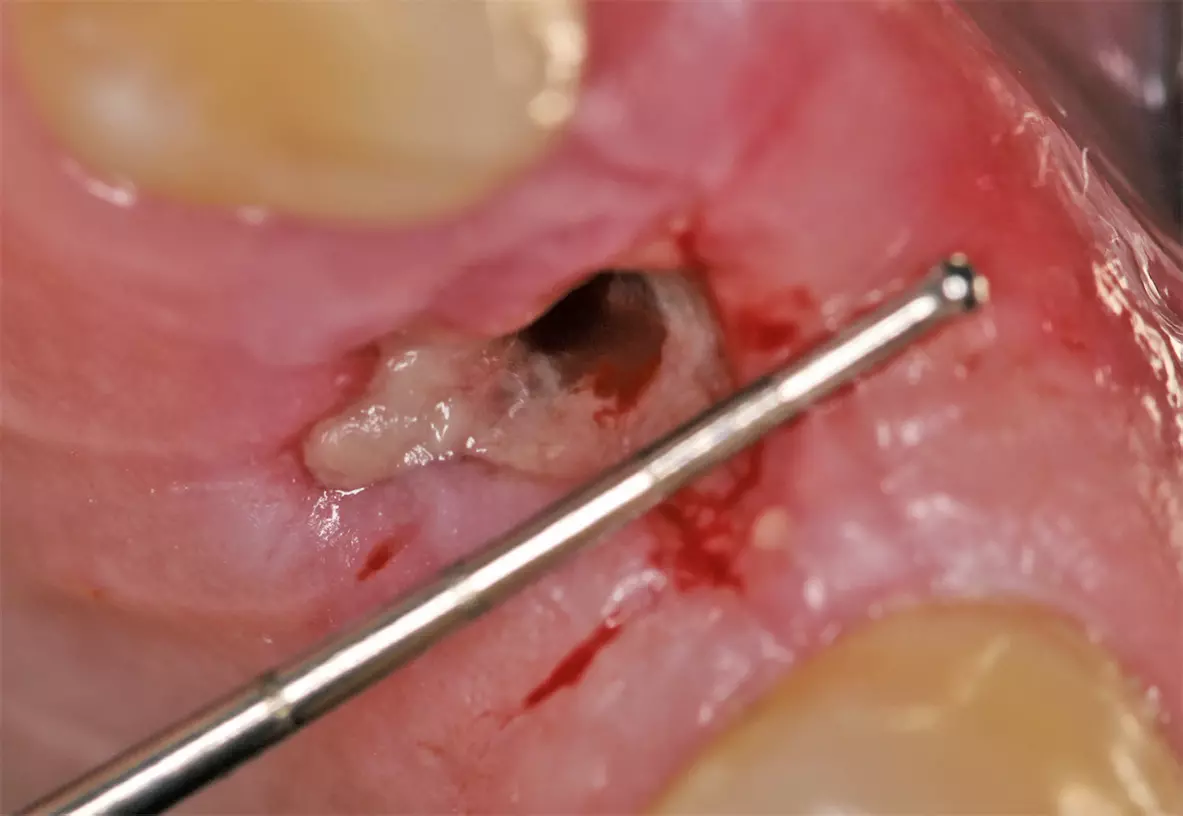

Nach ausführlicher Aufklärung und Beratung wurde die Extraktion des Zahnes 24 geplant. Zu diesem Zeitpunkt entschied sich der Patient gegen eine präventive Maßnahme zur Versorgung der Extraktionsalveole. Eine schonende Extraktion des Zahnes erfolgte komplikationslos unter gängiger Lokalanästhesie. Dabei konnte die vestibuläre Lamelle regelrecht erhalten werden (Abb. 2). Die Extraktionsalveole wurde mit einer Naht versorgt (Abb. 3). Ein Tag nach der Extraktion zeigt sich eine fibrinbelegte Wunde mit zeitgerechter und regelrechter Wundheilungsstatus (Abb. 4). Nach einer Woche wurde die Naht entfernt. Es zeigte sich zu diesem Zeitpunkt weiterhin eine fibrinbelegte Wunde mit einer okklusalen Mulde, die etwa 5 mm tief ist. Die Heilung war nach einer Woche also noch nicht komplett abgeschlossen (Abb. 5). In der frühen Wundheilungsphase berichtete der Patient beschwerdefrei gewesen zu sein. Drei Monate später stellte sich der Patient erneut vor mit dem Wunsch einen festsitzenden Zahnersatz zu bekommen. Die Extraktionsalveole zeigte eine vollständige Wundheilung und eine deutliche vestibuläre Knochenresorption (Abb. 6). Das Implantat konnte trotzdem eingesetzt werden und zeigt zum Zeitpunkt der Implantation eine adäquate Primärstabilität (Abb. 7). Nach drei Monaten wurde das Implantat freigelegt (Abb. 8) und anschließend mit einer Krone versorgt (Abb. 9).

Nach schonender Extraktion des Zahnes 24 unter Erhalt der vestibulären Lamelle wurden die PRF-Plugs in die Extraktionsalveole eingebracht (Abb. 14 und 15) und mit einer Naht fixiert (Abb. 16). Am ersten postoperativen Tag zeigte sich die Wunde reizlos und Fibrinbelegt (Abb. 17). In der ersten postoperativen Woche war die Patientin beschwerdefrei und hatte nicht von ausgeprägten Schwellungen oder Schmerzen berichtet. An Tag 7 war die Wunde vollständig geheilt und mit gesunder Gingiva überdeckt. Eine leichte Mulde von etwa 1 mm war noch zu beobachten (Abb. 18). Nach drei Monaten zeigten sich gesunde Weichgewebsverhältnisse, sowie ein weitgehend erhaltener Alveolarkamm mit leichter vestibulärer Einziehung (Abb. 19).